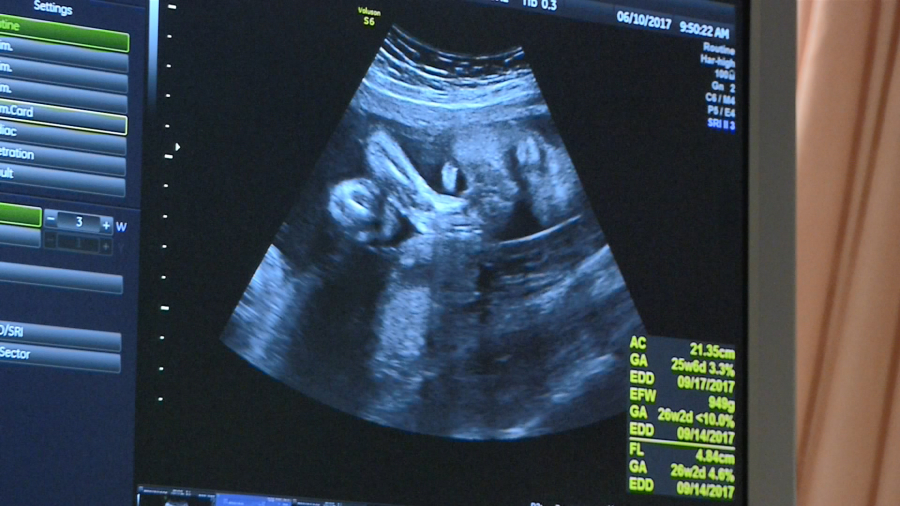

舊年中間,平均扯一千个幼嬰仔,佇咧生產的過程中,有超過4个會生了無順序,來過身。是10冬來,上蓋懸的比例。婦產科的醫師是講,主要就是現代人生產率降低,尤其"高齡產婦"又閣濟,才會發生意外的機會,嘛略仔會較加。

晚婚、晚孕的人愈來愈多,根據內政部統計,台灣女性生育第一胎,平均年齡落在30.9歲,而超過35歲的高齡產婦,10年來增加了1.59倍!婦產科醫師表示,產婦年齡越高,寶寶死產與早產機率也較高。

根據衛福部最新統計數據,2018年嬰兒死亡率,每千活產為4.2,而孕產婦死亡率,每十萬活產為12.2,雙雙創下10年新高。其中孕產婦死亡率,更是2001年以來最高。